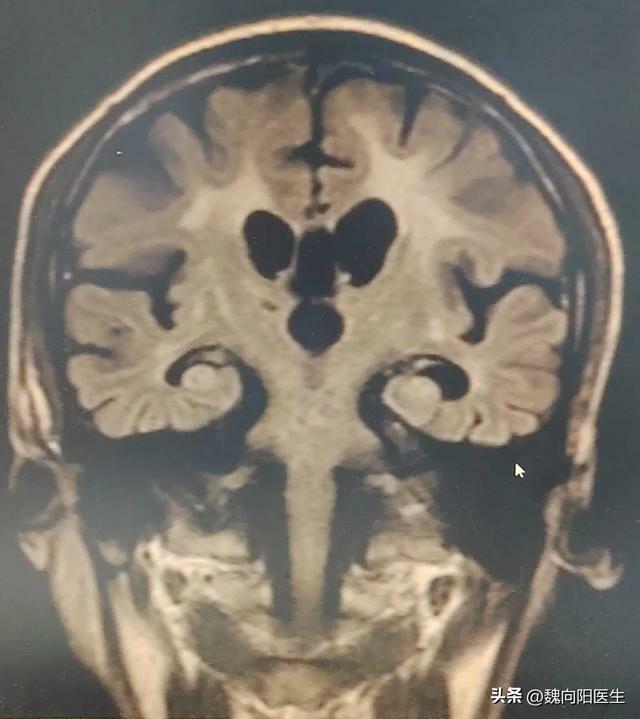

在醫院之後,我給患者進行了MoCA量表和MMSE檢測,結果提示患者已經處於中重度痴呆狀態,屬於典型的阿爾茲海默病。

阿爾茨海默病是老年人的腦部疾病,患者的腦細胞會急速退化,但並不是正常的衰老過程。

阿爾茲海默疾病

阿爾茲海默病占老年痴呆的一半以上,多發生於大於65歲以上的人群,痴呆的發生呈進行性加重的過程,剛開始起病不易察覺,發展緩慢,最早期往往是以逐漸加重的健忘開始,甚至有些老年人表現為脾氣性格的改變出現心煩易怒,變得「內向」、多疑,不喜與人交流,喜歡自己一個人獨處。